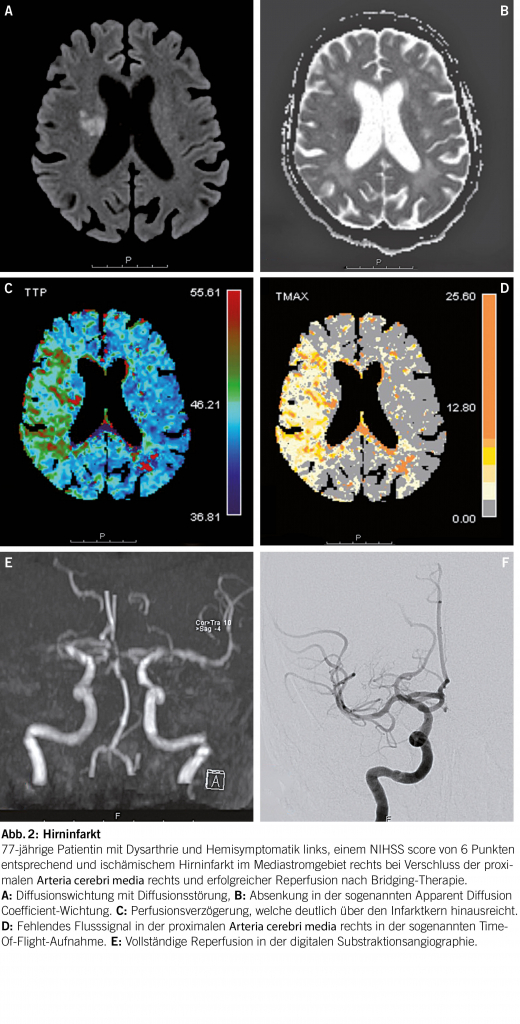

Arterielle Hypertonie verursacht einen Umbau der Gefässwand, fördert Atheromatose und Veränderungen der Endothelfunktion sowie der zerebralen Autoregulation. In der Folge entstehende Gefässrupturen führen zu Hirnblutungen (Abb. 1). Embolien, lokale Thrombusbildung oder seltener eine hämodynamische Insuffizienz verursachen Hirninfarkte (Abb. 2). Durch chronische mikroangiopathische Schäden entstehen Marklagerhyperintensitäten, Mikroinfarkte/-blutungen und neurodegenerative Prozesse wie Hirnatrophie. Es steigt nicht nur das Hirnschlag- aber auch das Demenzrisiko vom vaskulären aber auch vom Alzheimer Typ (8, 9).